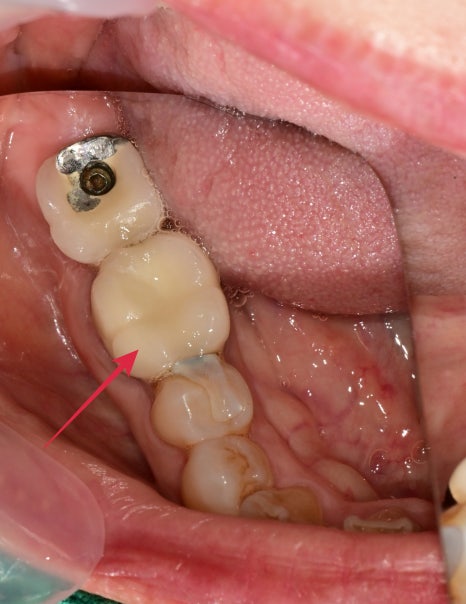

치아 부분이 계속 붓고 양치할 때 시큰해요

해당 어금니 부분의 잇몸이 붓고 양치할 때 건들면 시큰하다는 증상으로 내원해 주셨습니다.

큰 엑스레이상에서 확인할 때 과거에 크라운치료를 받은 치아의 뿌리 주변이 염증소견이 보였습니다.

10개월이 지난 후 찍은 엑스레이 사진과 구내 사진입니다

증상은 치료 전과 비교했을 때 통증이나 불편감은 없으시다 하셨고

뿌리 주변의 염증소견도 나아진 상태입니다.

치료전 염증이 컸던 치아라 걱정하며 주기적으로 체크를 하는 중인데

다행히 잘 유지되고 있습니다.